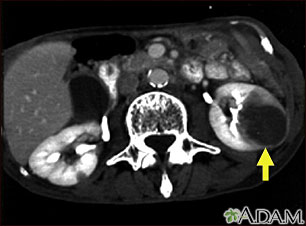

TC del abdomen medio de un paciente con carcinoma pulmonar que muestra metástasis (cáncer diseminado) hacia el riñón izquierdo. Obsérvese el tumor del riñón, al lado derecho de la imagen, de forma circular, grande y oscuro.